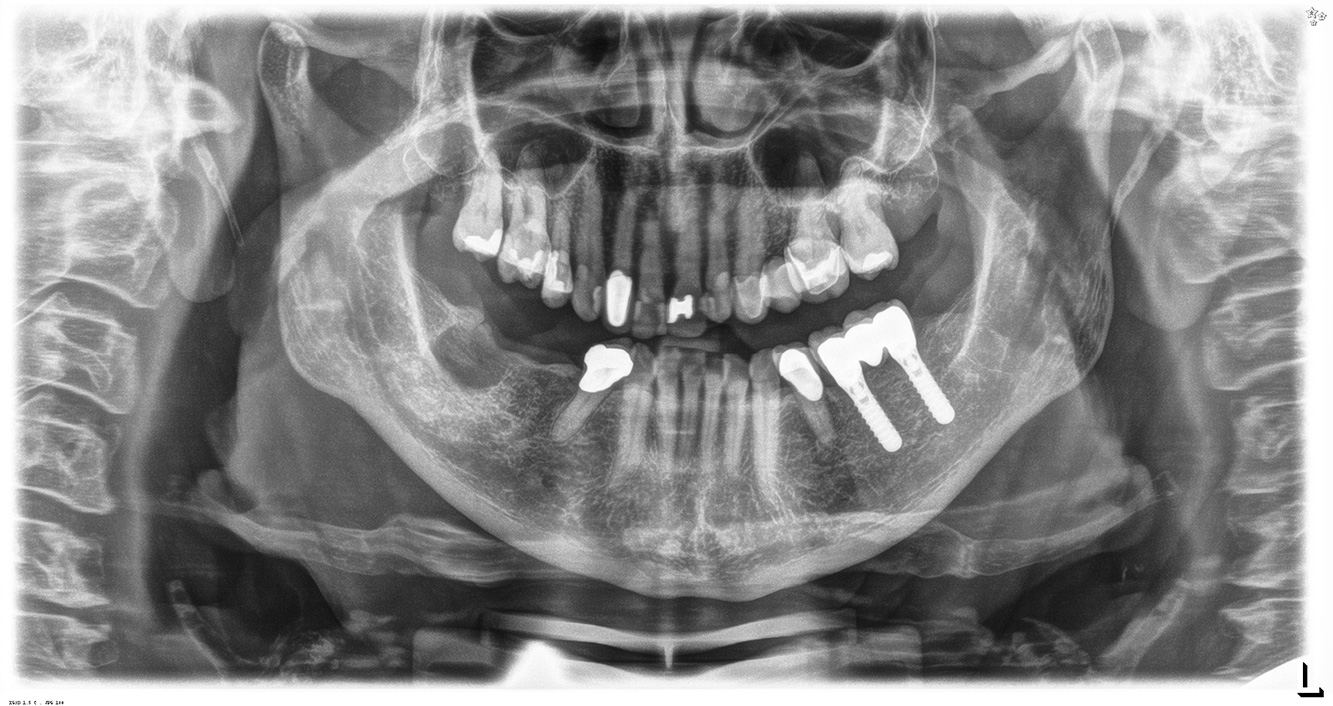

Casi di pazienti secondo l'IPCI seguenti studi di casi servono a mostrare l'interazione tra i fattori di bisogno e di rischio definiti per l'IPC così come gli effetti dei singoli fattori*. La paziente diabetica con una buona igiene oraleUna paziente diabetica di 51 anni con una buona igiene orale si presenta per una seduta di prevenzione. I valori di glicemia sono stabili con HbA1c = 6,2%, per cui si ritiene che la sua condizione possa essere sufficientemente gestita con la metformina (un farmaco per il trattamento del diabete). La paziente non presenta restauri esistenti o precedenti patologie orali. Sulla base dei referti disponibili si può constatare una gengivite nonostante una condizione altrimenti stabile. di più Case presentation: Complex Dental Prosthesis ManagementThe direct relationship between intraoral and general health, as well as the bidirectional influence that they may have on one another, is well-known (1,2). It is absolutely essential to consider both factors when planning preventive intraoral measures and treatment in the dental practice. The primary objective is the maintenance of patient health and quality of life from both dental and medical perspectives. more The (orally) healthy patient with implantsIn the medical history, the 55-year-old patient states that he has no systemic disease and is not taking any medication. The patient’s lifestyle is similarly unremarkable. The patient has a few tooth restorations and two implants (2nd and 4th quadrants). On the basis of current findings, gingivitis is identified in an otherwise stable periodontal condition on the reduced periodontium (stage III, grade A). more The healthy patient with pre-existing periodontal disease & peri-implantitisA 52-year-old patient presents at a preventive care session. The patient has no systemic disease and is not taking any medication. He has had various dental treatments and also has two active carious lesions. In addition, the patient has four implants (2nd, 3rd and 4th quadrants). He is revealed to have early periodontal disease (stage IV, grade B). His periodontal condition is stable; a probing depth of Probing depths (ST) of 5 mm is only evident at the implant in region 36. Gingivitis is also identified. more The Diabetic Patient with Pre-Existing PeriodontitisThis case report of a 52-year-old male with type 2 diabetes and periodontitis emphasizes personalized preventive measures and periodontal health maintenance to manage the moderate disease progression risk. more The 28-Year-Old Cigarette Smoker with Dental Erosions28-year-old patient, smoker, with erosions. The bidirectional relationship between oral and general medical health is very well known. It is no longer sufficient – and arguably even old-fashioned – to consider intraoral conditions in isolation. In order to create a personalized, case-specific preventive and patient profile, it is essential to take a detailed medical history and perform diligent examination of the general medical and intraoral health, as well as considering the two in combination. more Il paziente affetto da endocardite con lesioni cariose attiveIl paziente ha 39 anni e in passato è stato sottoposto ad un intervento per la sostituzione della valvola aortica dovuta a insufficienza valvolare ed endocardite. Assume regolarmente l'ASS 100 come anticoagulante. Per quel che riguarda lo stile di vita, il regime alimentare seguito dal paziente è classificato come “dieta che favorisce la formazione della carie”, per via del consumo regolare di cibi ad alto contenuto di zuccheri e dei sei-sette pasti consumati al giorno. La salute orale del paziente indica un rischio moderato di carie, con lesioni attive. Il rischio di parodontite è basso, tuttavia il paziente è affetto da gengivite. Si formulano quindi i seguenti consigli per il trattamento di profilassi. di più Il paziente trapiantato con iperplasia gengivaleSi presenta un paziente di 71 anni che ha subito un trapianto di reni e con anamnesi di ipertonia (ipertensione). Considerata la sua storia clinica, serve una terapia a lungo termine con ciclosporina che ha un effetto immunosoppressivo e amlodipina che è specifica contro l'ipertensione. Il paziente riporta anche gengive sensibili e sanguinanti. Per quanto riguarda invece lo stato di salute orale, il paziente ha un restauro, presenta un'iperplasia gengivale marcata, una parodontite allo stadio II, grado B con tasche attive e un'iniziale carie radicolare al dente 22 e in più mancano otto denti. Dalla valutazione del rischio di carie si evince un rischio moderato di carie (API 60). Per la seduta di profilassi si possono formulare i seguenti consigli per il trattamento. di più La paziente sana con precedente patologia parodontaleQuesta paziente di 68 anni non presenta alcuna patologia precedente né segue alcuna terapia che possano ritenersi rilevanti dal punto di vista odontoiatrico, e il suo stile di vita non comporta alcun rischio particolare. La paziente ha due impianti (3° quadrante, da cinque anni) e una precedente patologia parodontale (parodontite allo stadio IV, grado B) con perdita del dente. Al momento le condizioni parodontali sono stabili, tuttavia la parodontite aumenta in misura significativa le complicazioni biologiche degli impianti e c'è dunque il rischio di perdita dell'impianto (21). Per la seduta di profilassi si possono formulare quattro consigli. di più